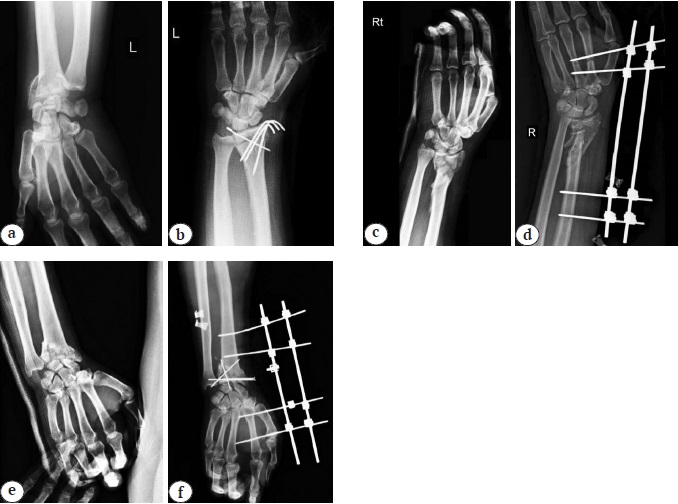

Radiographic indices have been compared between the study groups in Table 2. This table shows that although the four radiologic measures (radial inclination, radial height, ulnar variance and dorsal/palmar tilt) were in the normal clinical range after intervention, a significant statistical difference was observed between the three groups (p<0.001). Also, an example of radiographic images before and after the three mentioned procedures is shown in Figure 2.

Fig. 2. An example of radiographic images before and after the three surgical procedures: a — K-wire method before surgery; b — K-wire method after surgery; c — external fixation before surgery; d — external fixation after surgery; e — external fixation with pinning before surgery; f — external fixation with pinning after surgery